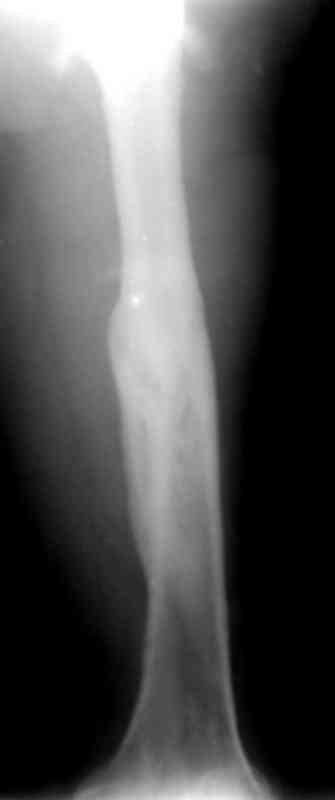

Больной А., 28 лет, поступил в НИИ им. Н.В. Склифосовского 22.12.99 после падения на улице. Жалобы на боли в области левого тазобедренного сустава и левом бедре. Из анамнеза следовало, что 20.06 во время прыжка с парашютом у него возник закрытый оскольчатый перелом средней трети левой бедренной кости со смещением отломков, по поводу чего в одной из ЦРБ Московской области через 3 дня после травмы был произведен открытый интрамедуллярный остеосинтез штифтом типа Кюнчера.

по его наружной поверхности послеоперационный рубец - рана зажила первичным натяжением. При измерении длины бедер обнаружено укорочение левого бедра на 4,5 см. На рентгенограммах этого бедра: ось конечности правильная, отмечается захождение основных костных фрагментов по длине, проксимальный конец штифта выступает слишком медиально и высоко относительно большого вертела, периостальная мозоль незначительна.22.12 - через 6 месяцев после операции, произведенной в ЦРБ, нами по поводу замедленно консолидирующего перелома левой бедренной кости с ее абсолютным укорочением под наркозом произведена операция: удаление штифта, закрытый блокирующий интрамедуллярный остеосинтез перелома левого бедра штифтом без рассверливания (UFN) длиной 40 см, диаметром 10 мм с блокированием только проксимальных отверстий (динамический остеосинтез). Наложен аппарат Илизарова на 4 полукольцах с целью удлинения укороченного бедра. Послеоперационное течение без особенностей. Ежедневно осуществляли дистракцию отломков на 1 мм. Через 3 недели после операции больной выпи-сан на амбулаторное лечение с продолжением дистракции отломков. В течение 1,5